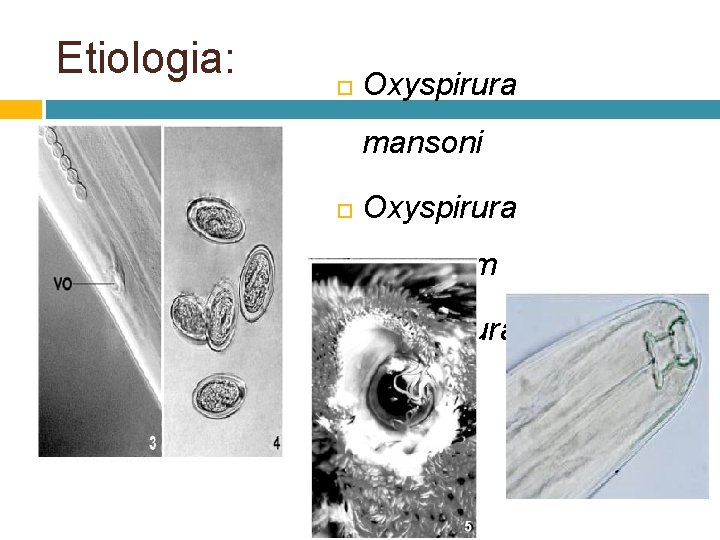

Etiologia: Oxyspirura mansoni Oxyspirura parvorum Oxyspirura petrowi

Localizacion: • Membrana nictitante • Conducto nasolagrima l • Sacos conjuntivos

Epidemiologia:

CB: Indirecto I Pycnoseleus surinamensis

Patogenia: A. Irritativa A. Inflamatori a A. Traumati ca

Sintomas y signos:

Diagnóstico: Heces: coprologico Observacion de los gusanos bajo membrana nictiante y saco conjuntivo.

Tratamiento:

Control: